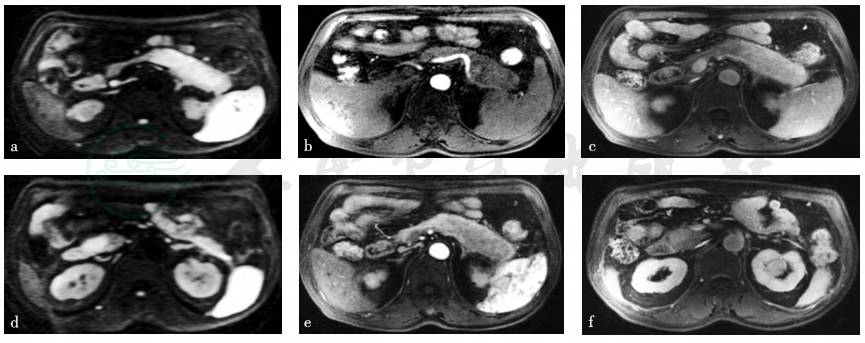

磁共振平扫+增强:增强扫描显示胰体尾部、胰头部病变强化程度及节律近似,动脉期呈轻度不均匀强化,静脉期持续强化,信号强度与正常胰腺实质相近或略高,延迟期呈相对较高信号。胰管未见扩张。脾动脉、脾静脉局部被包绕,前者管壁僵硬,管腔局部轻度狭窄,后者局部显示中断。诊断意见:胰头部结节影,胰体尾部肿大,伴脾动静脉受累,多考虑自身免疫性胰腺炎可能(图1)。

图1 磁共振成像[弥散加权成像技术(diffusion weighted imaging,DWI)、增强早期+晚期、门脉期]